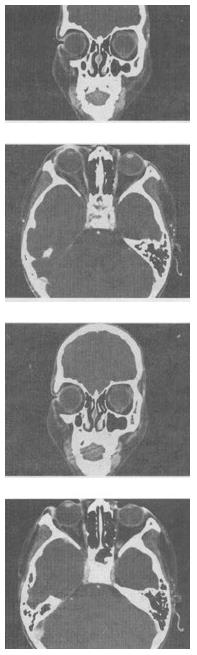

- 单项选择题 女,46岁,自述左眼视物不清3个月,CT扫描如图所示,正确的描述或诊断是()。

A、双侧眼球未见病变

B、左侧玻璃体内偏后方见絮状高密度影

C、双侧眼环形态密度正常

D、考虑视网膜脱离

E、考虑玻璃体内出血

- B